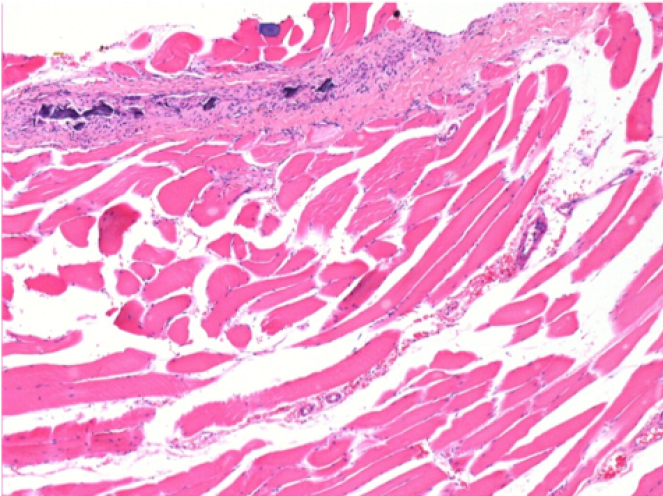

10 Inyección subcutánea

0,5 ml (5 x 0,1 ml) Endopeel SC Inyección en el área pretibial subcutánea derecha.

L:200x-Control-SC

R-D10-SC-200X

R-D30-SC-200X

R-D90-SC-200X

R-D210-SC-200X

R-D210-SC-400X